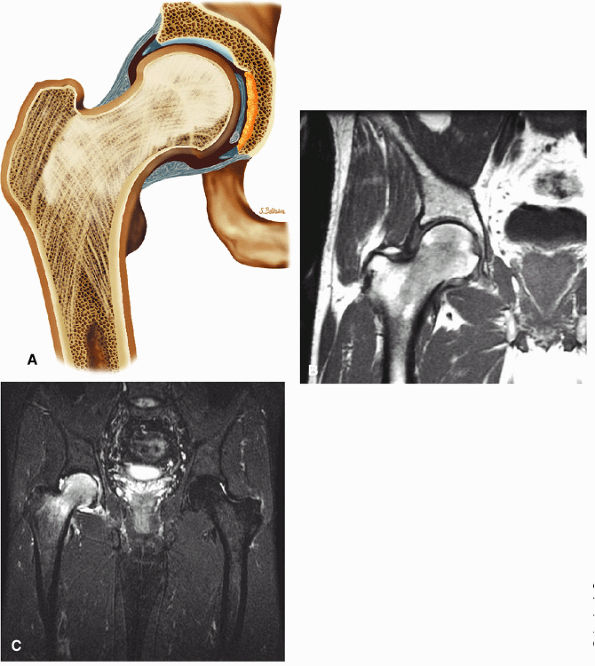

FIGURE 3.49 ● A normal cortical articular ridge of the acetabulum (arrow) is seen on (A) T2*-weighted coronal and (B) 3D CT images. This bony ridge should not be mistaken for osseous pathology. The acetabular notch (open arrow) is shown on the 3D CT rendering. (A: TR, 400 msec; TE, 20 msec; flip angle, 25°). (C) Arthroscopic view of acetabular notch.